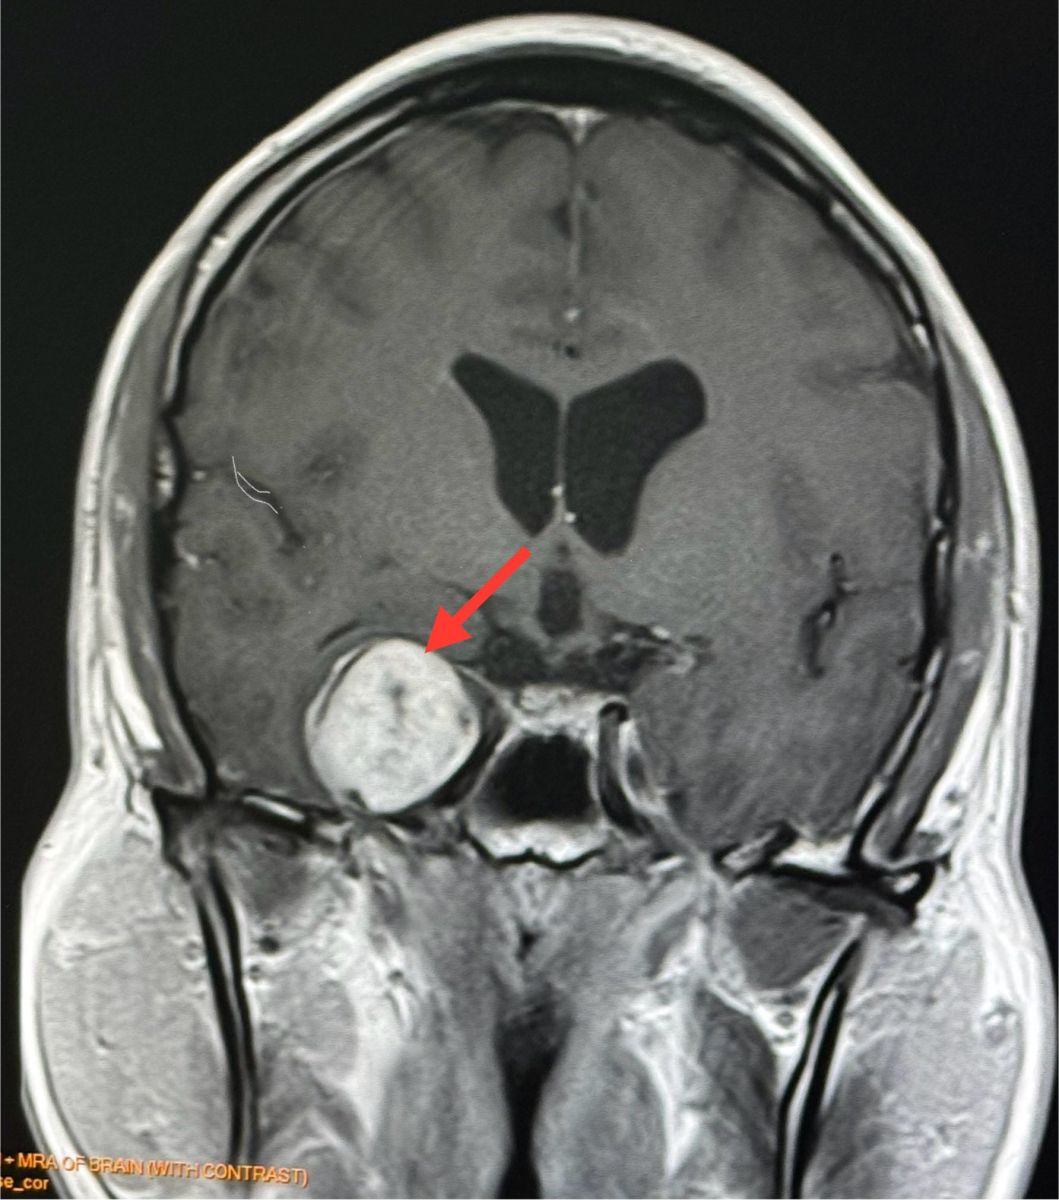

ทำคอมพิวเตอร์ CT สมองพบก้อนขนาด 2.7 × 3.0 × 2.9 เซนติเมตร ที่กลีบขมับของสมองด้านขวา right temporal lobe ทำ MRI (Magnetic Resonance Imaging) โดยใช้คลื่นแม่เหล็กไฟฟ้าและคลื่นวิทยุความถี่สูงและฉีดสี พบก้อนขนาด 3.1 × 2.9 × 2.9 เซนติเมตร สงสัย Trigeminal Schwannoma เนื้องอกของปลอกประสาทเส้นประสาทสมองเส้นที่ 5 ข้างขวา

อาการปวดศีรษะหายเอง ไม่ปวดอีกเลย ผู้ป่วยมีเนื้องอกในสมอง ตรวจเจอโดยบังเอิญจากการทำคอมพิวเตอร์สมอง